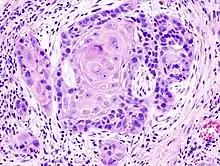

Squamous cell cancers are common in areas of the mouth, including the inner lip, tongue, floor of the mouth, gums, and hard palate. Cancers of the mouth are strongly associated with tobacco use, especially the use of chewing tobacco or dipping tobacco, as well as heavy alcohol use. Cancers of this region, particularly the tongue, are more frequently treated with surgery than other head and neck cancers. Lip and oral cavity cancers are the most commonly encountered types of head and neck cancer.[5]

Squamous-cell carcinoma

Squamous-cell carcinoma is a cancer of the squamous cell – a kind of epithelial cell found in both the skin and mucous membranes. It accounts for over 90% of all head and neck cancers,[59] including more than 90% of throat cancer.[23] Squamous cell carcinoma is most likely to appear in males over 40 years of age with a history of heavy alcohol use coupled with smoking.